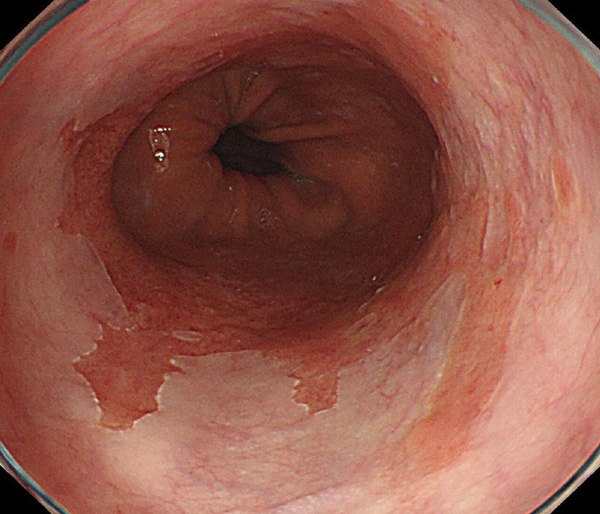

2026年1月24日開催の第19回研究会でご提示した検討症例です。 (画像をクリックすると拡大します)

2025年7月19日開催の第18回研究会でご提示した検討症例です。 (画像をクリックすると拡大します)

2025年1月11日開催の第17回研究会でご提示した検討症例です。 (画像をクリックすると拡大します)

2024年6月29日開催の第16回研究会でご提示した検討症例です。 (画像をクリックすると拡大します)

2024年1月6日開催の第15回研究会でご提示した検討症例です。 (画像をクリックすると拡大します)

2023年7月1日開催の第14回研究会でご提示した検討症例です。 (画像をクリックすると拡大します)

2023年1月21日開催の第13回研究会でご提示した検討症例です。 (画像をクリックすると拡大します)

2022年7月2日開催の第12回研究会でご提示した検討症例です。 (画像をクリックすると拡大します)

2022年1月22日開催の第11回研究会でご提示した検討症例です。 (画像をクリックすると拡大します)

2021年6月26日開催の第10回研究会でご提示した検討症例です。 (画像をクリックすると拡大します)

2021年1月23日開催の第9回研究会でご提示した検討症例です。 (画像をクリックすると拡大します)

2020年1月25日開催の第8回研究会でご提示した検討症例です。 (画像をクリックすると拡大します)

2019年1月12日開催の第6回研究会でご提示した検討症例です。 (画像をクリックすると拡大します)

2018年6月30日開催の第5回研究会でご提示した検討症例です。 (画像をクリックすると拡大します)

2017年7月15日開催の第3回研究会でご提示した検討症例です。 (画像をクリックすると拡大します)

2017年1月7日開催の第2回研究会でご提示した検討症例です。 (画像をクリックすると拡大します)

2016年6月4日開催の第1回研究会でご提示した検討症例です。 (画像をクリックすると拡大します)